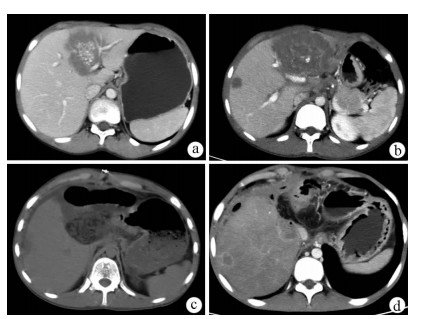

Primary fibrosarcoma of the liver misdiagnosed as hepatic abscess: A case report

Liuyang ZHU, Jiancun HOU, Long YANG, Wen TONG, Yamin ZHANG

2021, 37(7): 1665-1667. DOI: 10.3969/j.issn.1001-5256.2021.07.037

Abstract(896) HTML (266) PDF (3350KB)(81)

Abstract: